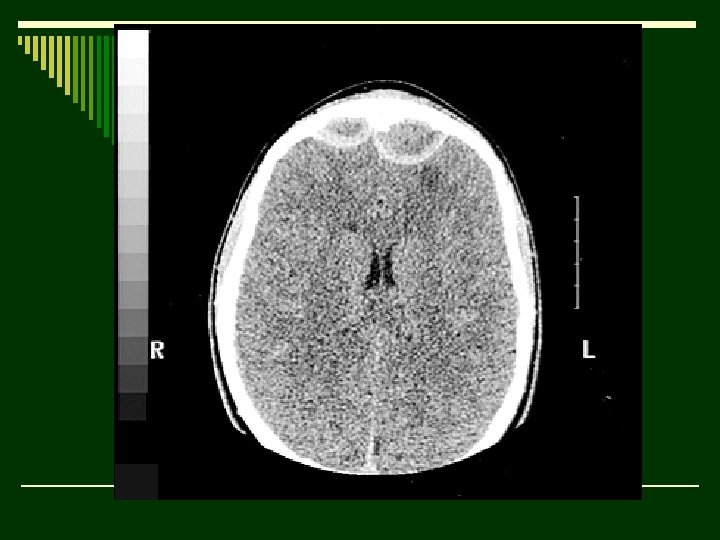

Hydrocephalus, air-encephalography. o The ventricles are outlined by air that has been exchanged for cerebro- spinal fluid, via lumbar puncture. The patient is anaesthetised erect. After sub-arachnoid air injection, change of position of the patient allows views to show different structures. In this view, air has outlined the posterior sections of the dilated lateral ventricles and the 'low' density above the pituitary fossa is air in the posterior part of the third ventricle. o Additional densities are iodinated oil run-up from the lumbar region in a previous assessment of the posterior fossa and now remains in recesses in the basal cisterns. o Very expensive and complex machines designed to allow invasive procedures to be performed, while moving the patient in different planes and allowing X-rays to be taken, at the same time. Compared with Computed tomography in a usually ambulant patient the information from these complex examinations now seems a limited return for the investment.